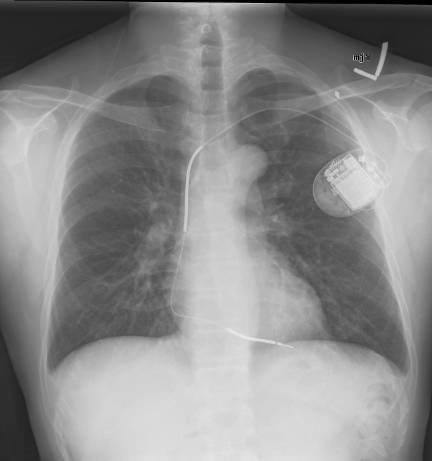

En el seguimiento a 13,9 años del ensayo clínico que comparó un desfibrilador automático implantable (DAI) con la terapia de resincronización cardíaca (TRC) en pacientes con insuficiencia cardíaca clase II o III de la NYHA, fracción de eyección menor al 30%  y QRS ancho, se comprombó que se mantenía significativa la reducción inicial de mortalidad asociada a la TRC en comparación con el DAI. New England Journal of Medicine, 18 de enero de 2024.